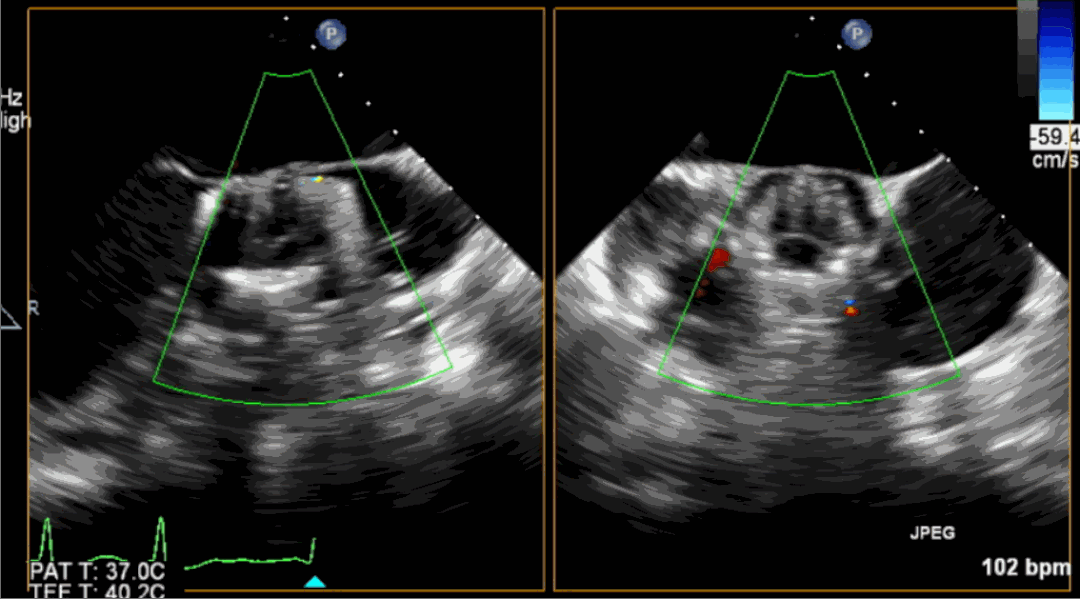

術前超聲影像圖

術后超聲影像圖